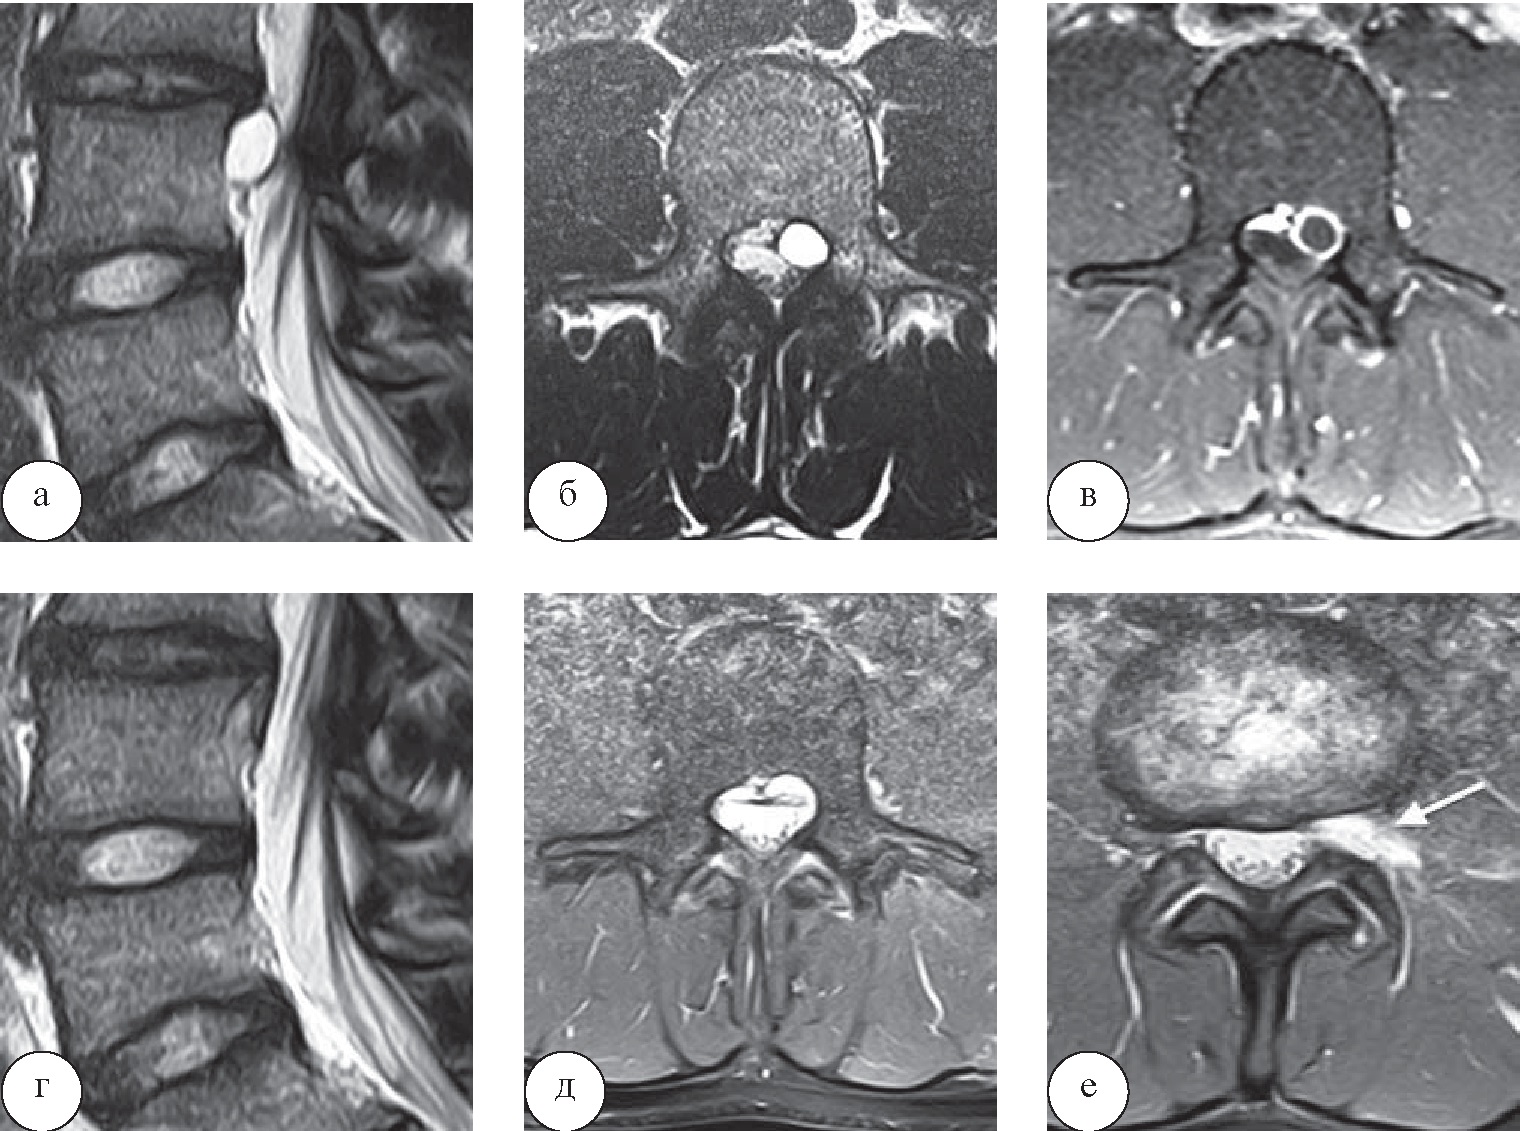

У 2 пациентов, страдающих кистами межпозвонковых дисков, применялось хирургическое лечение. В одном случае использовали традиционную микрохирургическую технику, идентичную поясничной микродискэктомии; в другом – перкутанное транс- фораминальное эндоскопическое вмешательство по вышеописанной методике (рис. 4).

Рис. 4. Перкутанное эндоскопическое трансфораминальное удаление кисты межпозвонкового диска LIII–LIV: а, б, в – дооперационные МРТ (а, б – сагиттальная и аксиальная МР-проекции (режимы Т2-ВИ), в – аксиальная проекция, Т1-ВИ с контрастом); г, д, е – МРТ через сутки после операции (в, г – сагиттальная и аксиальная МР-проекции (режимы Т2-ВИ), е – аксиальный срез (режим Т2-ВИ), стрелка – зона послеоперационных изменений в левом межпозвонковом отверстии)